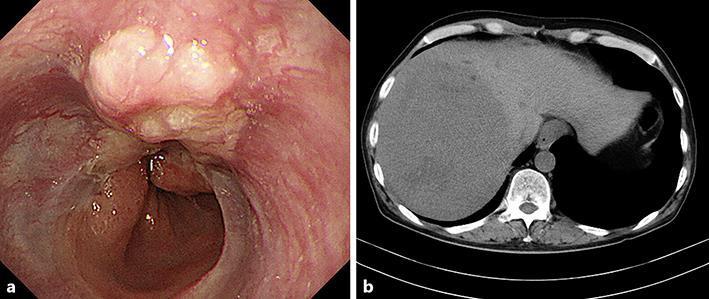

Esophageal large-cell neuroendocrine carcinoma (NEC) is a rare malignant tumor that is characterized by high-grade malignancy and a poor prognosis. However, the rarity of esophageal NEC has prevented the development of an established treatment, and no reports have described a discrepancy in the effectiveness of cisplatin plus irinotecan between primary and metastatic lesions. A 43-year-old Japanese man was referred to our hospital with refractory epigastralgia. A previous gastrointestinal endoscopy had revealed a 50-mm type 2 tumor in the abdominal esophagus. The pathological findings indicated poorly differentiated squamous cell carcinoma. Contrast-enhanced computed tomography revealed a metastatic liver tumor. One cycle of fluorouracil and cisplatin was not effective, and endoscopy was repeatedly performed. The pathological findings indicated a large-cell malignant tumor with tumor cells that were positive for CD56, synaptophysin, and Ki-67 (> 80%). Based on a diagnosis of esophageal large-cell NEC with a metastatic liver tumor, the patient received cisplatin plus irinotecan biweekly. After 4 months, computed tomography revealed marked shrinkage of the metastatic tumor, but the patient complained of dysphagia. Endoscopy revealed enlargement of the primary tumor, which was then treated using radiotherapy plus fluorouracil and cisplatin. The primary tumor subsequently shrank, and the patient's symptoms were relieved, but the metastatic tumor grew. Thus, chemoradiotherapy could be an option for managing a primary esophageal large-cell NEC that does not respond to chemotherapy alone. However, the possibility of an inconsistent response to therapy in primary and metastatic lesions should be considered.

食管大细胞神经内分泌癌(NEC)是一种罕见的恶性肿瘤,其特点是恶性程度高、预后差。然而,食管NEC的罕见性阻碍了既定治疗方法的发展,且尚无报道描述顺铂联合伊立替康在原发性和转移性病变中的疗效差异。一名43岁的日本男性因难治性上腹痛转诊至我院。先前的胃肠内镜检查发现腹部食管有一个50毫米的2型肿瘤。病理结果显示为低分化鳞状细胞癌。增强计算机断层扫描显示有肝转移瘤。氟尿嘧啶和顺铂的一个疗程治疗无效,遂反复进行内镜检查。病理结果显示为大细胞恶性肿瘤,肿瘤细胞CD56、突触素和Ki-67呈阳性(>80%)。基于食管大细胞NEC伴肝转移瘤的诊断,患者接受顺铂联合伊立替康的双周治疗。4个月后,计算机断层扫描显示转移瘤明显缩小,但患者出现吞咽困难。内镜检查显示原发性肿瘤增大,随后采用放疗联合氟尿嘧啶和顺铂进行治疗。原发性肿瘤随后缩小,患者症状缓解,但转移瘤增大。因此,放化疗可能是治疗对单纯化疗无反应的原发性食管大细胞NEC的一种选择。然而,应考虑原发性和转移性病变对治疗反应不一致的可能性。